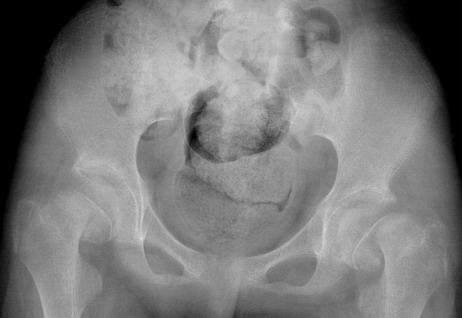

13岁女孩,主因两腿不能分2天就诊.追问病史:曾因癫痫发作,家人按髋部病史.既往史:生理发育欠佳,智力有障碍,说话不清.

左侧股骨头骨骺明显向下移,考虑左侧股骨头骨骺分离。右侧显示欠清,注意排除同时存在右侧股骨头骨骺分离。

双侧颈干角无明显变化 双髋外展位,不支持髋内翻畸型。结合病史考虑神经性骨关节病可能要大。

双侧股骨头骨骺分离

较支持双侧股骨头骨骺明滑脱。